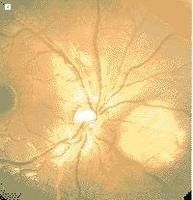

迴旋狀脈絡膜視網膜萎縮2.眼底改變 早期患者眼底赤道部出現邊界清楚的脈絡膜萎縮斑,形狀不規則、邊緣呈鋸齒狀,萎縮斑之間眼底正常。以後萎縮斑緩慢擴展,散在的萎縮斑逐漸融合成片,呈花環狀,並向後極及周邊部延伸擴展,亦可在視盤周圍形成一個萎縮環 此環與赤道部的萎縮環之間可形成一個有視功能存在的環形區域,最後眼底呈黃白色,幾乎所有的眼底範圍受損,僅保留黃斑區(圖1A)。此時眼底所見與無脈絡膜症者相似。視盤呈蠟黃色或淡紅色。晚期病例可出現色素增生,其間散布有針尖狀結晶。另外,視網膜血管細窄、視盤蒼白。在大多數40~60歲的晚期病例中後極部脈絡膜視網膜廣泛受累,眼底外觀類似於晚期無脈絡膜症。